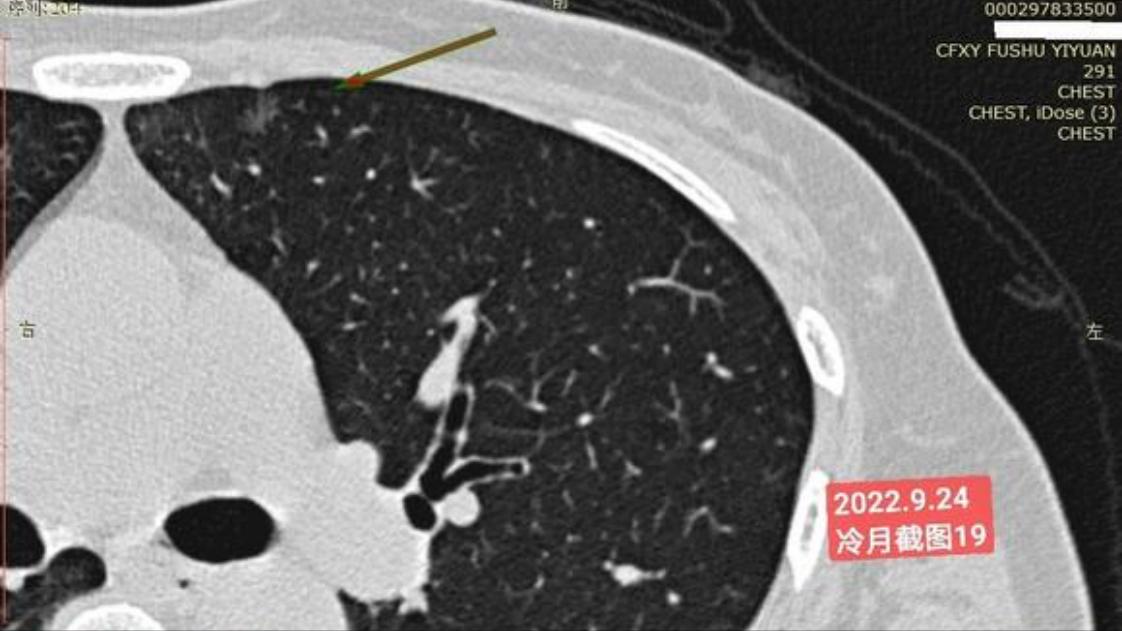

我是21年7月做肺部CT,报告给报出0.5厘米肺结节。(但大夫说,20年就已经有那个肺结节了,因为小,报告没给报)。自发现肺结节后,吃了四个月中药,结节没有缩小,反而增大了。今年8月1日开始到现在,又吃了近两个月的蒙药了。 结节还是没有缩小,反而在增大。21年7月到现在,复查过3次肺部CT了。结节一直在增大。最近一次复查时间是2022年9月24日。

上次找戴主任贴吧咨询过,主任说我右肺下叶那个结节高危,距离上次CT,到现在三个月复查肺部CT。所以9月24日又复查做了肺部CT。

右下肺结节高危,肺窗已经到亚实性阶段CTR>0.5,纵膈窗可见实性,目前已经不属于异质混磨,而且PSN亚实性结节。